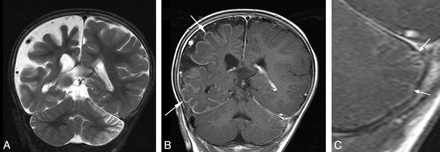

Pial angioma involving both supra- and infratentorial compartments. A and B, T1WI postgadolinium MR images of different patients (8 and 5 months of age, respectively) demonstrate pial enhancement of the left cerebral hemisphere (white arrows) and midbrain bilaterally (arrowheads). Choroidal angiomas (black arrow) and choroid plexus hypertrophy were also evident localized to the side of supratentorial involvement.

Coronal MR images of an 8-month-old boy. A, T2WI image demonstrates atrophy of the right cerebral hemisphere and left cerebellar hemisphere. B, T1WI postgadolinium image demonstrates pial enhancement of the right cerebral hemisphere (white arrows) and left cerebellar hemisphere. C, Magnified T1WI postgadolinium image of the left cerebellar hemisphere demonstrates enhancement of the pial surface of the folia (white arrows). Bilateral midbrain pial enhancement and choroid plexus hypertrophy were also evident in this case.